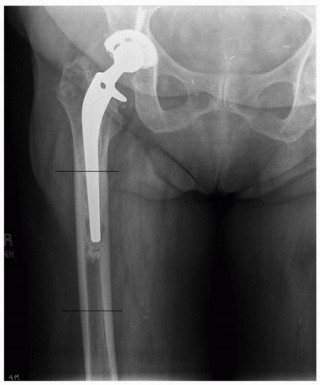

PERIPROSTHETIC FRACTURES TOTAL HIP ARTHROPLASTY Femoral Shaft Fractures Epidemiology Intraoperative: There is…